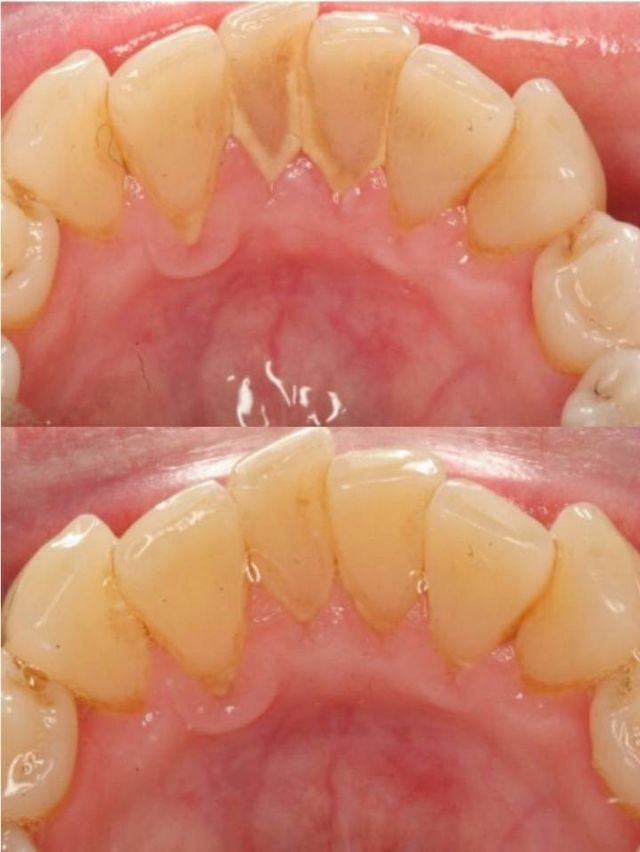

치석이 잘 쌓이는 데

특히 아랫니 뒤

여기 침샘 분비되어서

치석 잘 쌓인대

평소 내눈에 안보여서 그렇지

저기 보통 치석 광산임

치아 사이도 사이지만

잇몸과 치아 사이에는 잘 보일꺼임

지 치석을 보고 스케일링 안가면 그거 문제있음.

더러워서 당장 치과로 뛰쳐나가고싶음

치과사진에서 가져옴

아래 하얀 부분이 치석이야

담배피면 치석 갈색 검은색임.

오래되어도 치석 검게 변함.